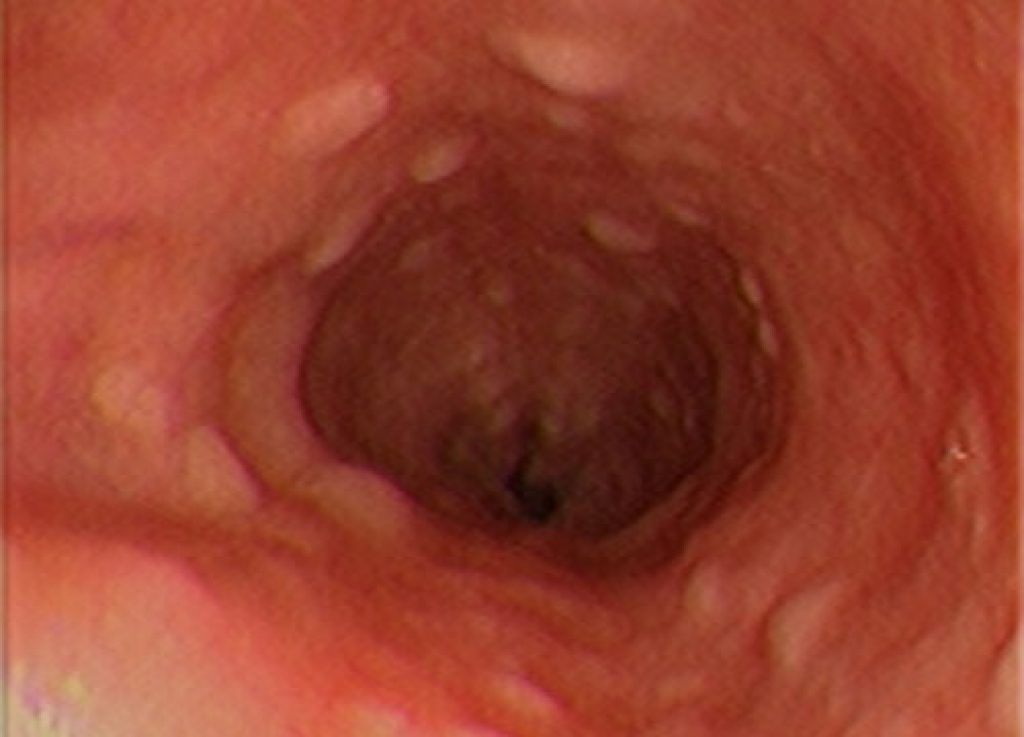

The research group, led by Professor H. Phillip Koeffler, Senior Principal Investigator at CSI Singapore and Deputy Director of NCIS, has conducted a comprehensive genomic study of esophageal squamous carcinoma, a type of very aggressive cancer prevalent in Singapore and Southeast Asia.

In this study, the researchers investigated a large variety of genetic lesions which arose from esophageal squamous carcinoma. The results showed enrichment of genetic abnormalities that affect several important cellular process and pathways in human cells, which promote the development of this malignancy. The scientists also uncovered a number of novel candidate genes that may make the cancer sensitive to chemotherapy.